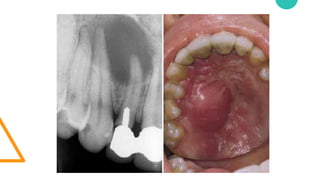

• Dolor tanto de la pieza dental como de la

zona dañada por la caries.

• Hinchazón y enrojecimiento de la encía

debido a la infección.

• El dentista mediante una exploración de la

zona y una radiografía determinará el

alcance del daño y decidirá el tratamiento

más adecuado.